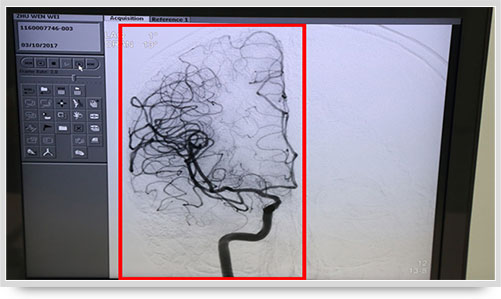

同时,手术台前的液晶显示仪屏幕上清晰地现显出导管的路径,在李主任的操作下准确到达指定检查部位,各条血管的“庐山真面目”清晰可见。

全脑血管造影术(DSA)是运用数字减影技术下进行的全脑血管摄片,因此又称数字减影血管造影。技术上一般采用局部麻醉,右侧股动脉穿刺、置管,再将一根造影管通过腹主动脉、主动脉弓,选择性进入左右颈内动脉和椎动脉后,分别造影,发现病灶后还应行三维血管造影。造影图像较以往所用的常规脑血管造影所显示的图像,更清晰和直观,一些精细的血管结构亦能显示出来,是目前国际上公认的血管性疾病诊断的“金标准”。

弓上造影、超选到颈内动脉、椎动脉......在数字减影技术下,注入显影剂后,导管经患者右侧股动脉在体内推进,由于股动脉离脑血管距离较远,中间“路程复杂”,对施术医生的要求非常之高。